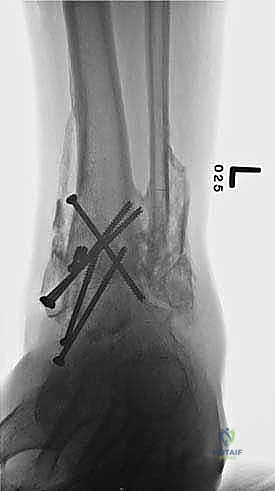

| طرق العلاج | أدوية مضادة للالتهابات (NSAIDs)، أحذية طبية مخصصة (Rocker-bottom shoes)، دعامات الكاحل (AFO)، حقن الكورتيزون أو البلازما (PRP)، العلاج الطبيعي. | جراحة إزالة الغضاريف التالفة ودمج العظام (Arthrodesis) باستخدام مسامير وألواح معدنية. |

- تثبيت ميكانيكي حيوي أقوى: يتيح المدخل الأمامي وضع شريحة معدنية (Anterior Plate) على الجانب الأمامي للمفصل. من الناحية الميكانيكية الحيوية (Biomechanics)، يعتبر الجانب الأمامي هو "جانب الشد" (Tension side) أثناء المشي. وضع الشريحة هنا يوفر تثبيتاً فائق القوة ويقلل من معدلات عدم الالتئام.

- التخطيط الجراحي الرقمي: باستخدام صور الأشعة المقطعية، يقوم الدكتور هطيف بتخطيط الجراحة على الكمبيوتر لاختيار حجم المسامير والشرائح المناسبة بدقة مليمترية.

خطوات جراحة تثبيت مفصل الكاحل الأمامي بالتفصيل (Step-by-Step Surgical Procedure)

تُجرى العملية تحت التخدير العام أو النصفي (الشوكي)، وتستغرق عادةً بين ساعتين إلى ثلاث ساعات، وتتطلب دقة ومهارة فائقتين. إليكم الخطوات الجراحية كما ينفذها الأستاذ الدكتور محمد هطيف:

1. الوضعية والشق الجراحي (Positioning and Incision)

يستلقي المريض على ظهره (Supine position). يتم استخدام عاصبة (Tourniquet) حول الفخذ لتقليل النزيف وتوفير رؤية واضحة. يقوم الدكتور هطيف بإجراء شق طولي أمامي فوق مفصل الكاحل، عادة بين وتر العضلة الظنبوبية الأمامية (Tibialis Anterior) ووتر العضلة الباسطة الطويلة لإصبع القدم